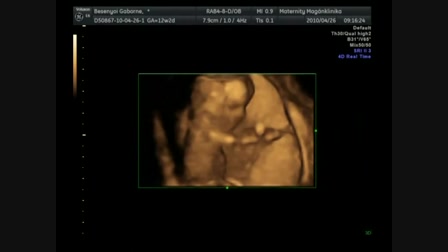

Lilivel Egerben voltunk, ahol ilyen is volt...